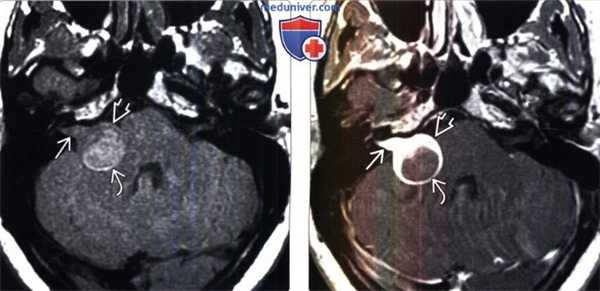

(Слева) МРТ, Т1-ВИ, аксиальный срез: в области ВСП и ММУ определяются соответствующие компоненты крупной вестибулярной шванномы. Повышение сигнала в участке опухоли, расположенном в медиальной части ММУ, обусловлено присутствием метгемоглобина вследствие подострого внутриопухолевого кровоизлияния.

(Справа) МРТ, постконтрастное Т1 -ВИ, аксиальный срез: у этого же пациента определяется контрастирование компонентов вестибулярной шванномы в области ВСП и ММУ. Наличие интрамурального кистозного компонента В в медиальной области ММУ обусловлено кровоизлиянием.